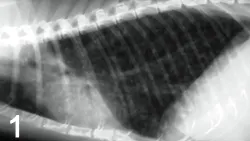

The most common radiographic change common to both feline asthma and bronchitis is peribronchial cuffing, often described as doughnuts or tram lines (Figure 1). Other common causes of cough and increased respiratory effort include pneumonia, heart failure, cancer, and heartworm disease. These disorders usually create radiographic abnormalities that differ from the classic findings of hyperinflation and bronchial markings seen in chronic bronchitis or asthma.

Figure 1. This lateral thoracic radiograph demonstrates classic features of feline asthma, including hyperinflation and peribronchial infiltration (doughnuts and tram lines).